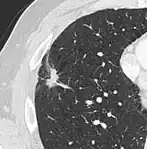

- Margin morphology: a spiculated margin is a risk factor for cancer.[8] Benign causes tend to have a well defined border, whereas lobulated lesions or those with an irregular margin extending into the neighbouring tissue tend to be malignant.[10] In particular, spiculations are highly predictive of malignancy with a positive predictive value up to 90%.[9] Also, a "notch sign", which is an abrupt indentation of the nodule, increases the risk of cancer, but may also be found in granulomatous diseases.[9]

subpleural nodule.[9] -